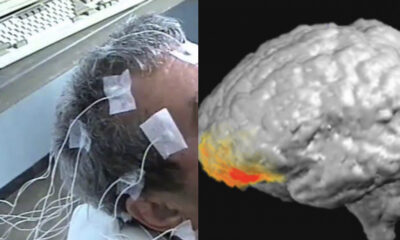

Cientistas israelenses conseguiram mapear o exato momento em que um homem judeu de 46 anos tem um encontro espiritual com Deus. As informações são da Discovery...